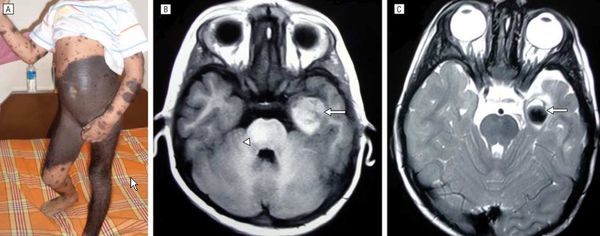

Нейрокожный меланоз

В редких случаях развивается нейрокожный меланоз — заболевание, при котором меланоциты разрастаются в центральной нервной системе. К таким нарушениям может приводить мутация гена BRAF [50] .

Факторы риска развития нейрокожного меланоза:

- гигантский невус на спине (более 40 см);

- множественные невусы-спутники — чем их больше, тем выше риск;

- более двух средних невусов, особенно если помимо них много других невусов.

В исследовании американских учёных меланоз диагностировали у 26 из 379 пациентов с большими врождёнными невусами [12] . Заболевание может протекать без симптомов и случайно выявляться при МРТ, но в некоторых случаях оно сопровождается неврологическими нарушениями:

Неврологические симптомы могут развиться из-за кровоизлияния в желудочки головного мозга, нарушения циркуляции спинномозговой жидкости, сдавления спинного мозга или злокачественного перерождения меланоцитов [3] [14] .

Симптомы появляются примерно в двухлетнем возрасте. Прогноз чаще неблагоприятный, даже если нет злокачественных новообразований [15] . В одном обзоре были изучены 39 случаев симптоматического нейрокожного меланоза: более половины пациентов погибли в течение трёх лет после появления неврологических нарушений [34] .